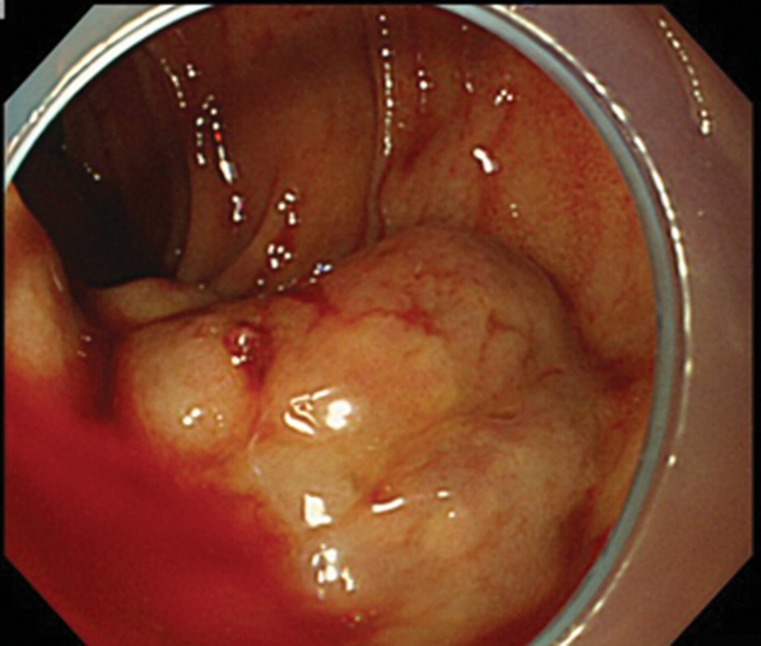

十二指肠静脉曲张是异位门静脉系统分流,不容易导致胃肠道出血。球囊闭塞逆行经静脉闭塞术是治疗胃静脉曲张的常用方法。我们报告一位60岁男性患者,由于起源于胰十二指肠下静脉的十二指肠静脉曲张破裂而导致黑黑;引流到性腺静脉。他的十二指肠静脉曲张破裂成功治疗双球囊闭塞栓塞治疗。

Duodenal varices are ectopic portosystemic shunts that do not tend to result in gastrointestinal bleeding. Balloon-occluded retrograde transvenous obliteration is an established treatment for gastric varices. We report a 60-year-old man with melena due to ruptured duodenal varices originating at an inferior pancreaticoduodenal vein; drainage was into a gonadal vein. His ruptured duodenal varices were successfully treated by dual balloon-occluded embolotherapy.